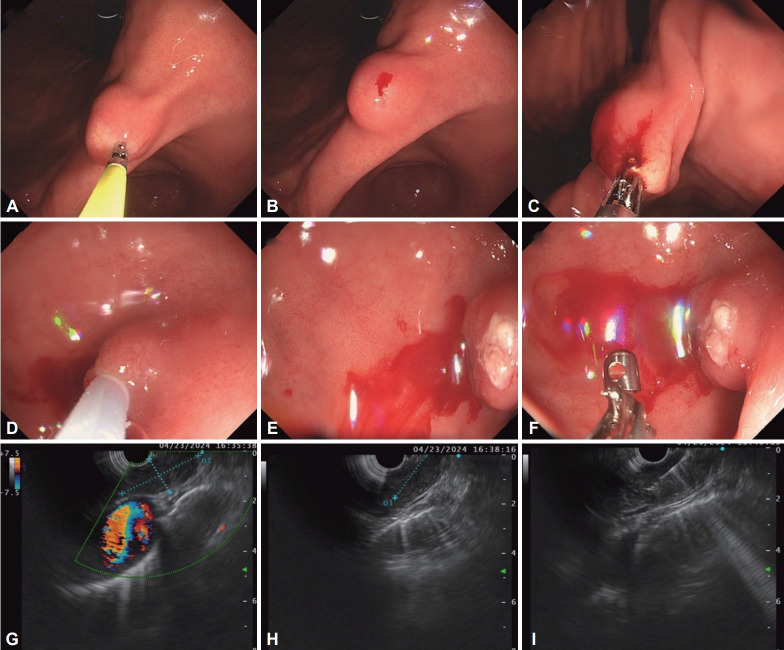

胃上皮下病变(SELs)的检测随着内镜筛查的广泛使用而增加。虽然大多数SELs是良性的,但有些,如胃肠道间质瘤,有恶性的可能,这强调了准确诊断的重要性。由于这些病变位于粘膜下,组织学确认往往具有挑战性,这限制了传统活检技术的有效性。超声内镜(EUS)在病变表征中起着核心作用,它提供了关于起源层、回声性和内部特征的信息。当需要组织取样时,粘膜切口辅助活检(MIAB)和eus引导的细针活检(FNB)等技术具有互补的优势。MIAB的诊断率约为89%,特别是对病变

The detection of gastric subepithelial lesions (SELs) has increased with the widespread use of endoscopic screening. While most SELs are benign, some, such as gastrointestinal stromal tumors, have malignant potential, underscoring the importance of accurate diagnosis. Histological confirmation is often challenging due to the submucosal location of these lesions, which limits the effectiveness of conventional biopsy techniques. Endoscopic ultrasonography (EUS) plays a central role in lesion characterization, providing information on the layer of origin, echogenicity, and internal features. When tissue sampling is required, techniques such as mucosal incision-assisted biopsy (MIAB) and EUS-guided fine-needle biopsy (FNB) offer complementary advantages. MIAB has demonstrated a diagnostic yield of approximately 89%, particularly for lesions <20 mm, whereas FNB provides sufficient tissue for immunohistochemical analysis. As international guidelines differ regarding indications and methods of tissue acquisition for SELs, tailored management based on EUS findings, patient-specific factors, and institutional capacity is essential for optimal diagnostic outcomes. This review aims to summarize the current understanding of gastric SELs based on evidence-based guidelines and recent studies and offer practical guidance for clinicians diagnosing these lesions in routine practice.